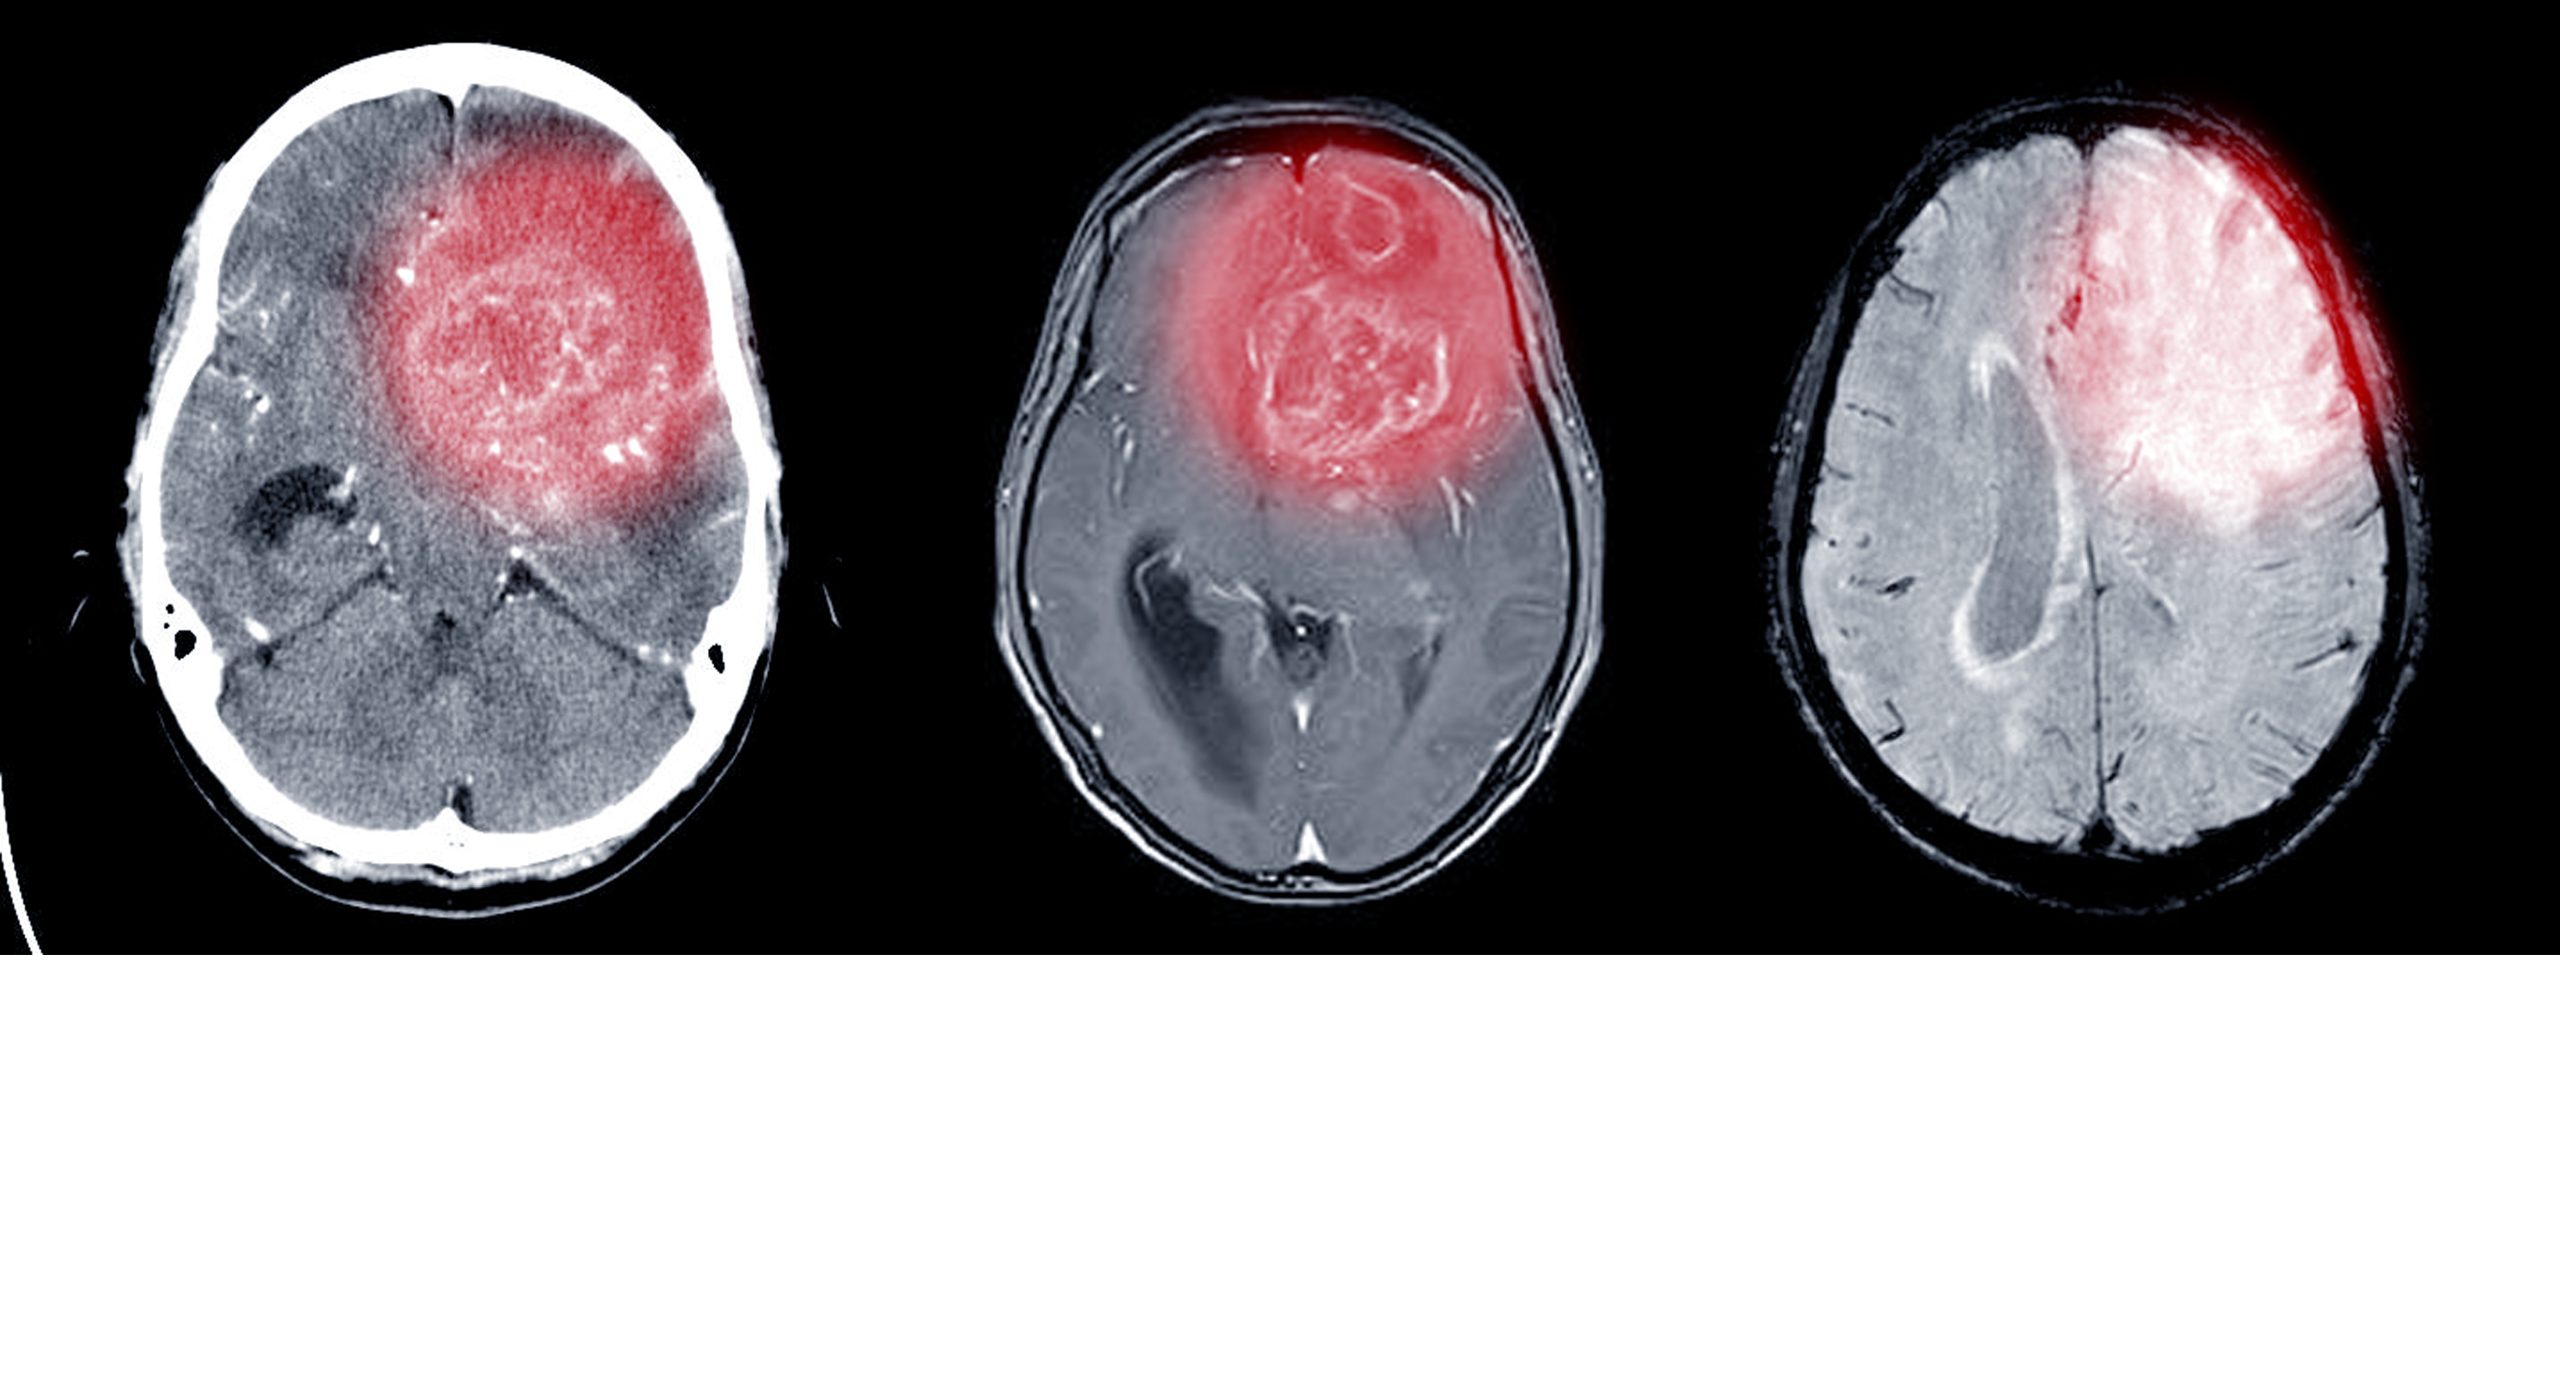

Οι επιστήμονες άρχισαν να χρησιμοποιούν τη μαγνητική εξέταση για να ερευνήσουν τη δομική εικόνα του εγκεφάλου σε εθελοντές που είχαν και που δεν είχαν δυσλεξία. Οι τρέχουσες τεχνικές απεικόνισης έχουν αποκαλύψει ότι υπάρχει λιγότερος όγκος φαιάς και λευκής ουσίας και ότι η ακεραιότητα της λευκής ουσίας στις ινιακές-κροταφικές και κροταφοβρεγματικές περιοχές του αριστερού ημισφαιρίου είναι αλλοιωμένη. Οι επιστήμονες εξακολουθούν να διερευνούν πώς αυτά τα ευρήματα επηρεάζονται από τη γλώσσα και τα διάφορα συστήματα γραφής.

Τα ευρήματα των μελετών που έχουν πραγματοποιηθεί σε πολλές χώρες συγκλίνουν στο ότι κάποιες περιοχές στο αριστερό ημισφαίριο του εγκεφάλου είναι αλλοιωμένες. Αυτές είναι η ινιακό-κροταφική περιοχή, η κροταφοβρεγματική περιοχή και ο κατώτερος μετωπιαίος φλοιός (μαζί με τις συνδέσεις αυτών). Τα αποτελέσματα των συγκεκριμένων μελετών επιβεβαιώνουν την καθολικότητα της δυσλεξίας σε διάφορες γλώσσες ανά τον κόσμο.